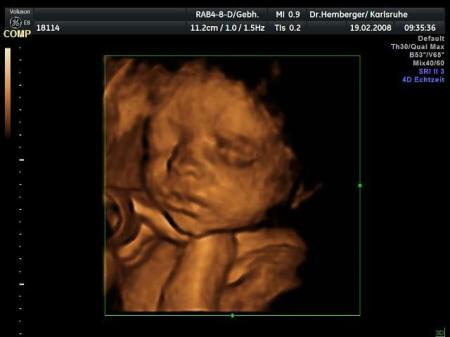

Ja das ist echt blöd; von meinen beiden Mädels hatte ich zu dem Zeitpunkt schon viel bessere Aufnahmen. Aber ich hab ab jetzt 2-wöchentlich VU-Termin, also gute Chancen, dass wir noch was bekommen bevor sie zu groß ist und die Chancen auf gute Bilder noch schlechter werden. Hier meine Große etwa um diesselbe SSW rum....